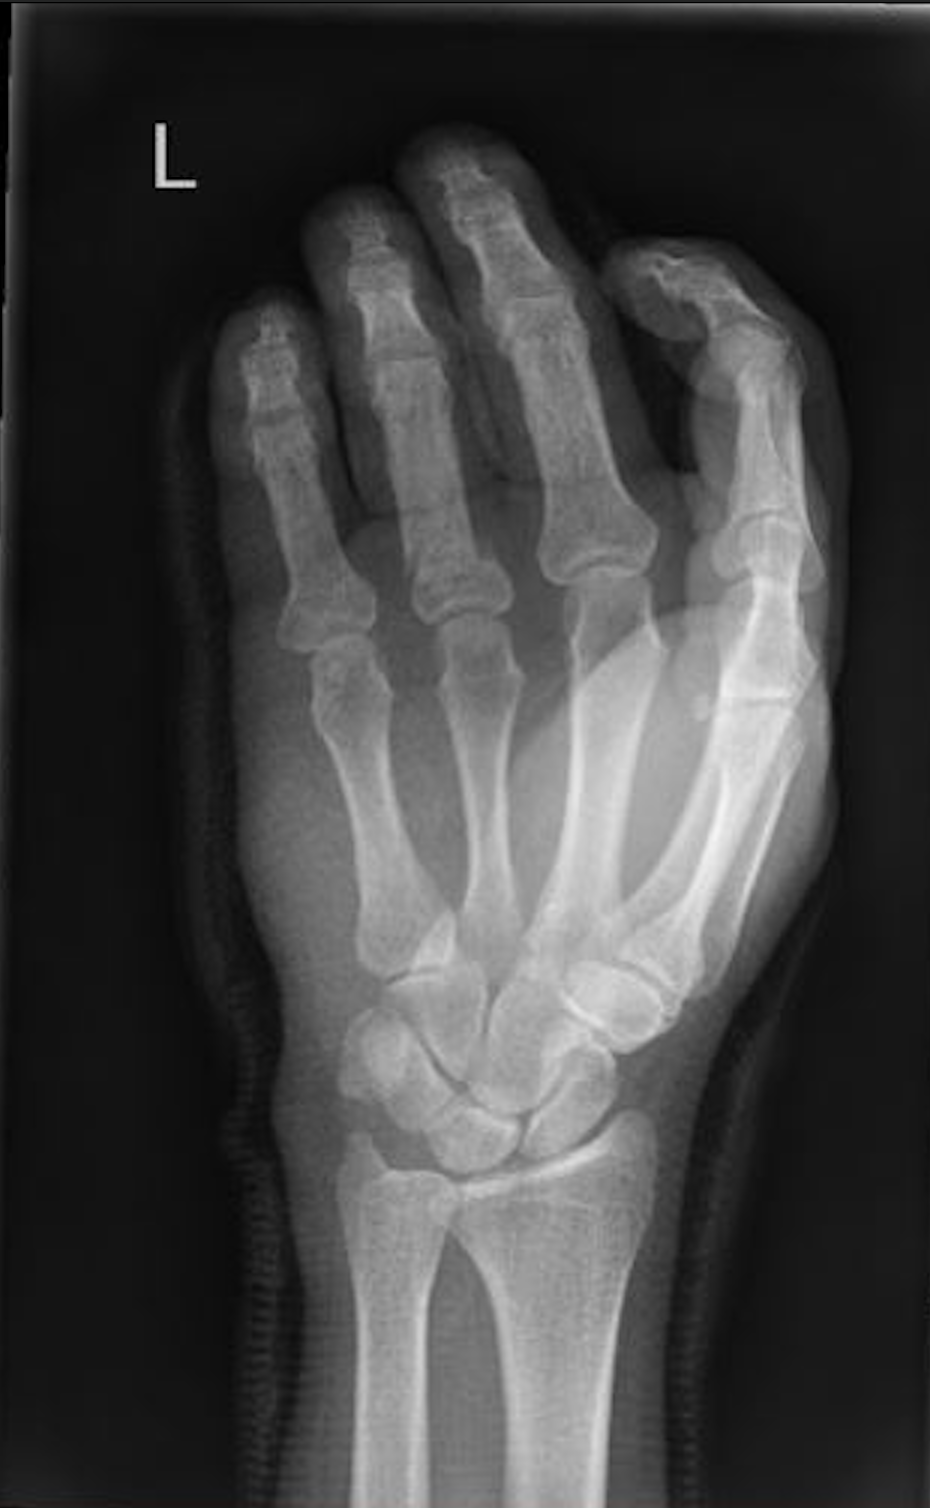

Re: Man en mes

511Ai Frans, pijnlijk. Mag je nog blij zijn dat je niet op ijs aan het schaatsen was. Dan was de kans dat het 'mes' iets met je vingers had gedaan! Beterschap.